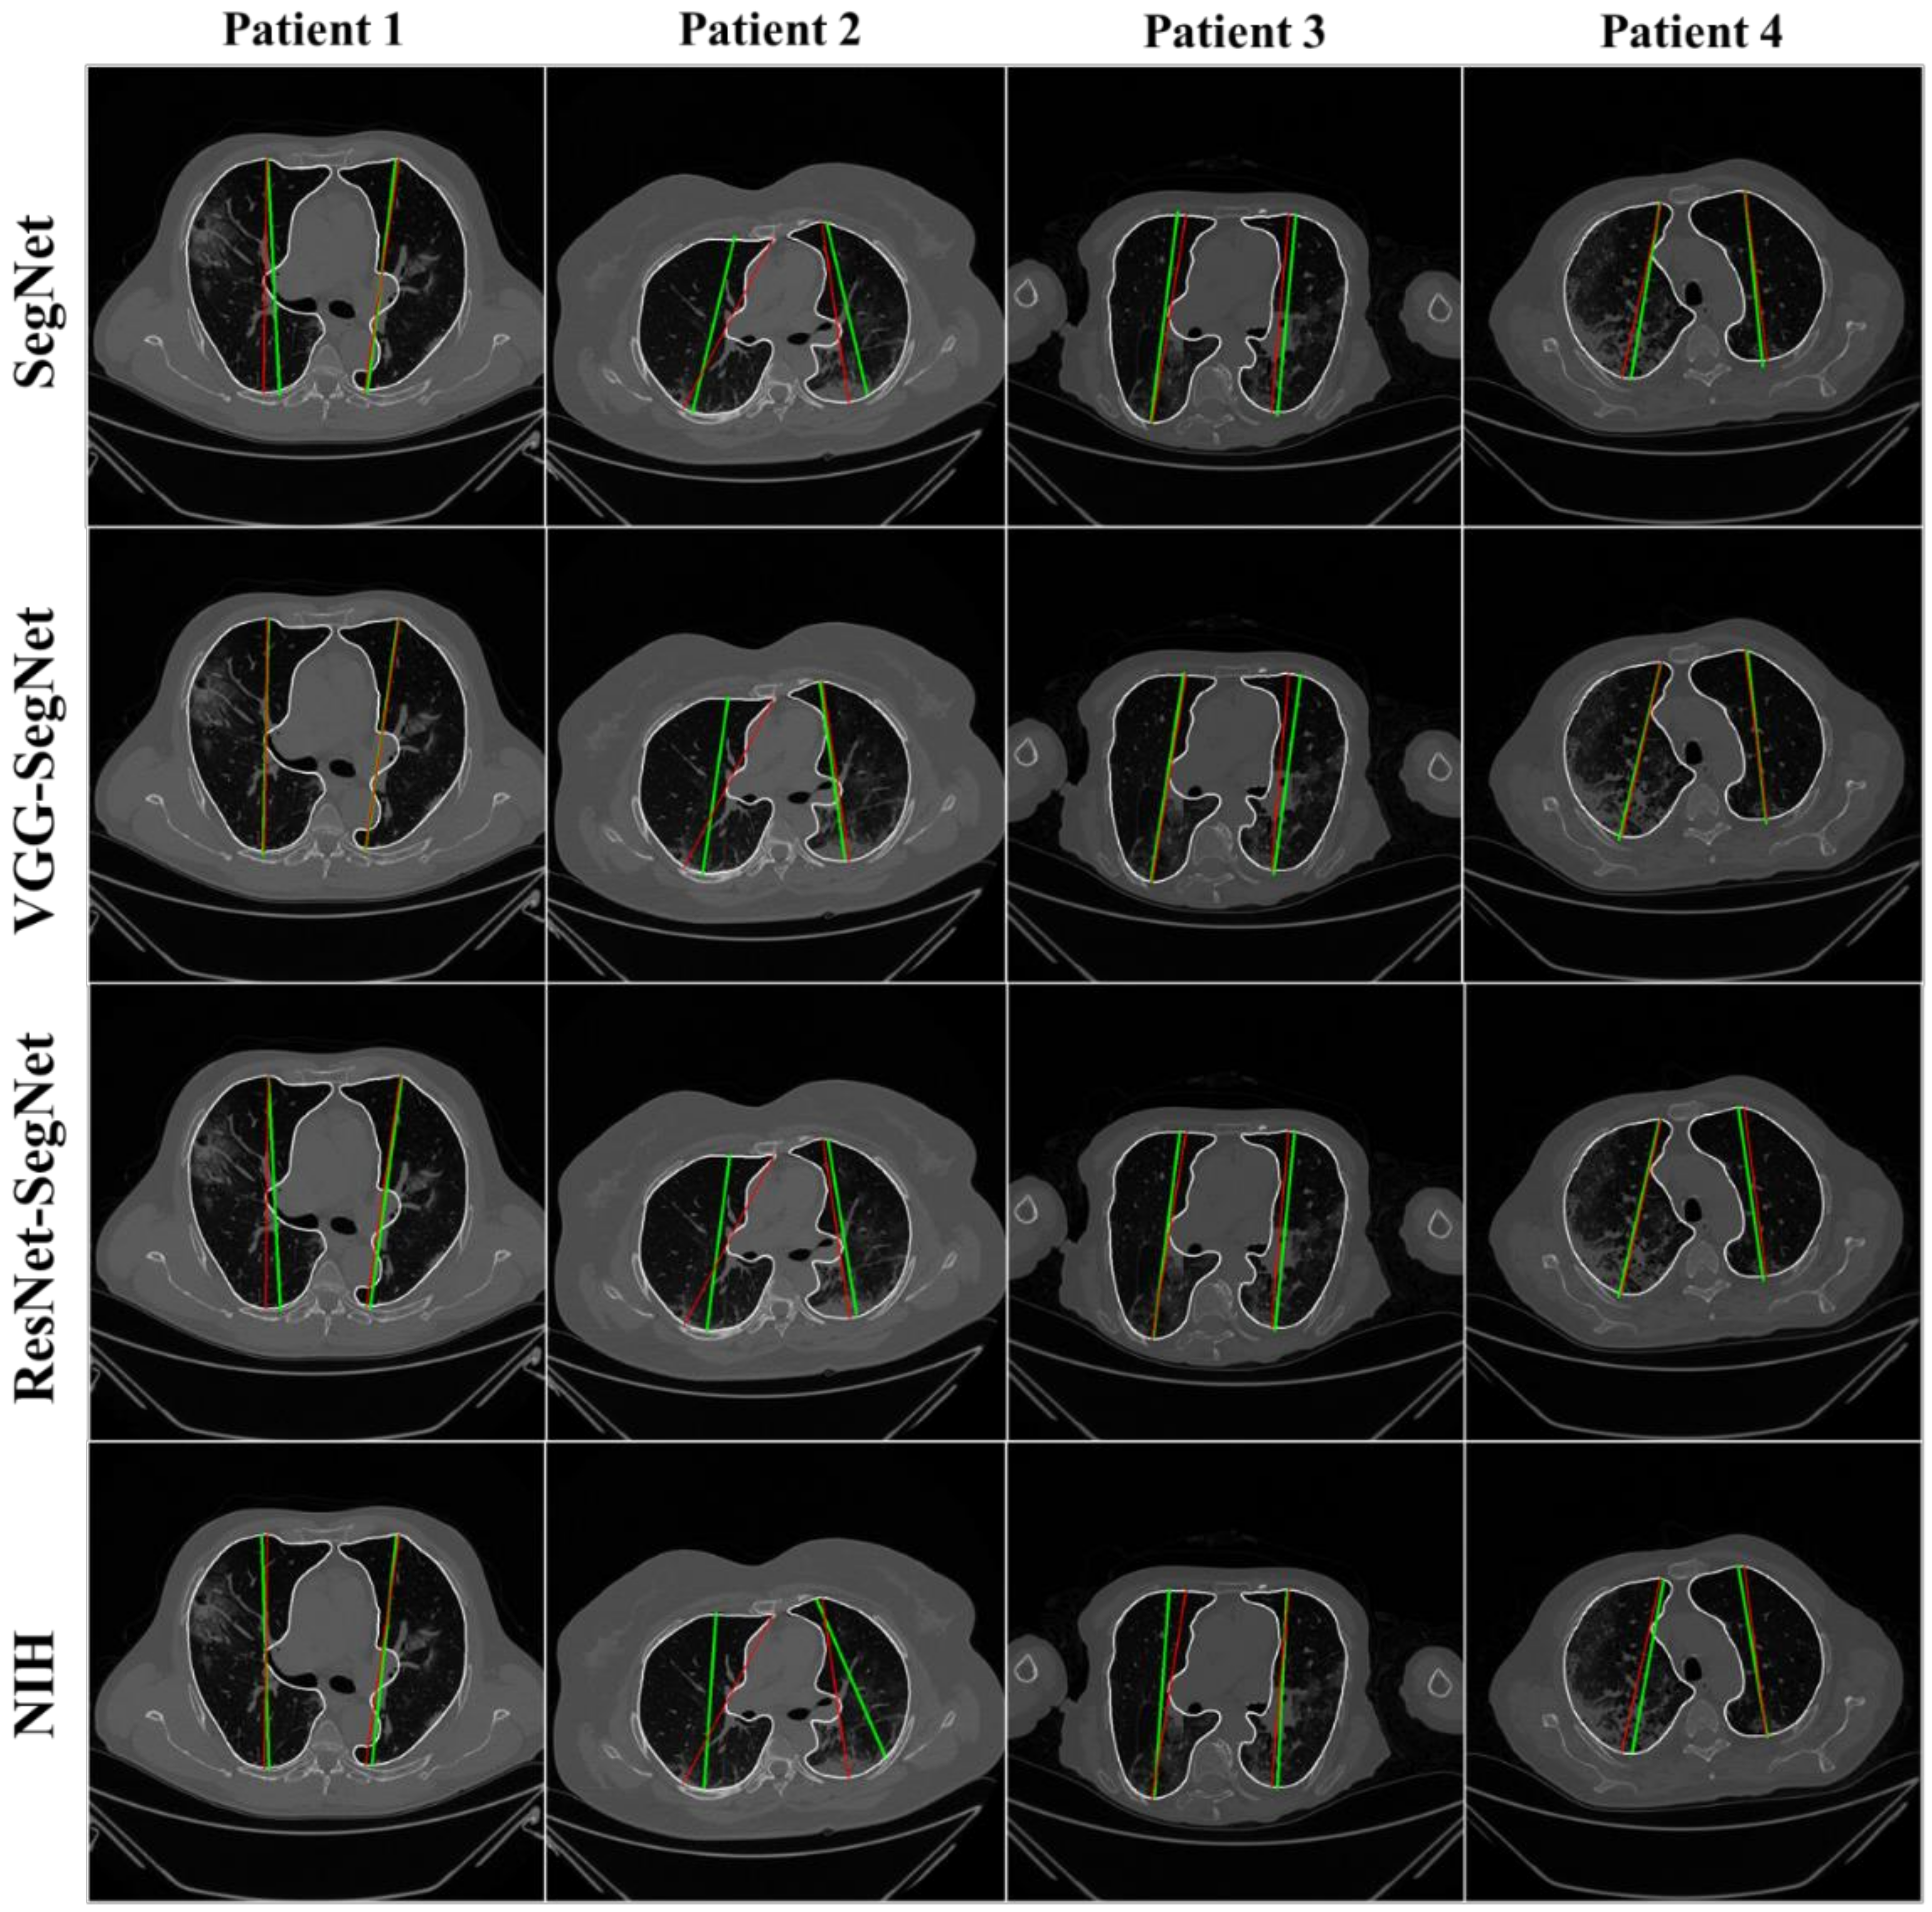

4.2.1. Visualization of Lung Boundary and Regional Lung Error

4.2.3. Performance Evaluation Using Lung Long Axis Error